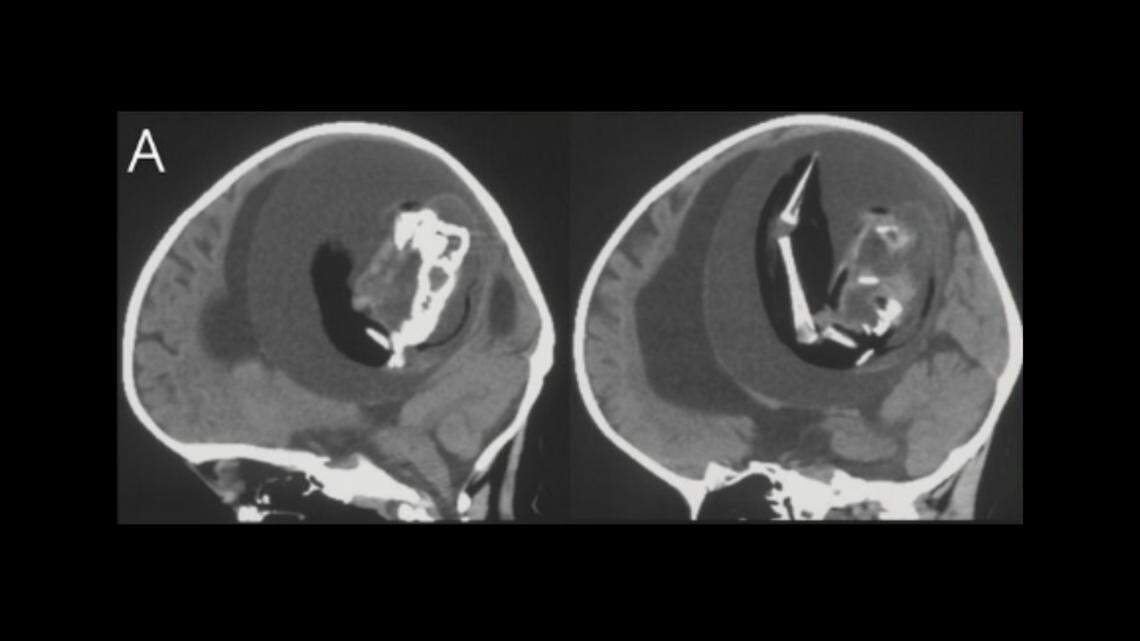

Inside the 1-year-old’s brain, doctors could see a spine and other bone structures.

Inside the 1-year-old’s brain, doctors could see a spine and other bone structures. Neurology

Doctors decided to take a closer look, and when they took an X-ray of her skull, they saw bones in a sac inside her brain.

What they removed was a fetus, about 10 centimeters long, with the beginning formations of arms and hands. The fetus had a spine, but remained extremely undeveloped. The doctors called it a “fetiform,” a type of growth that resembles a fetus.